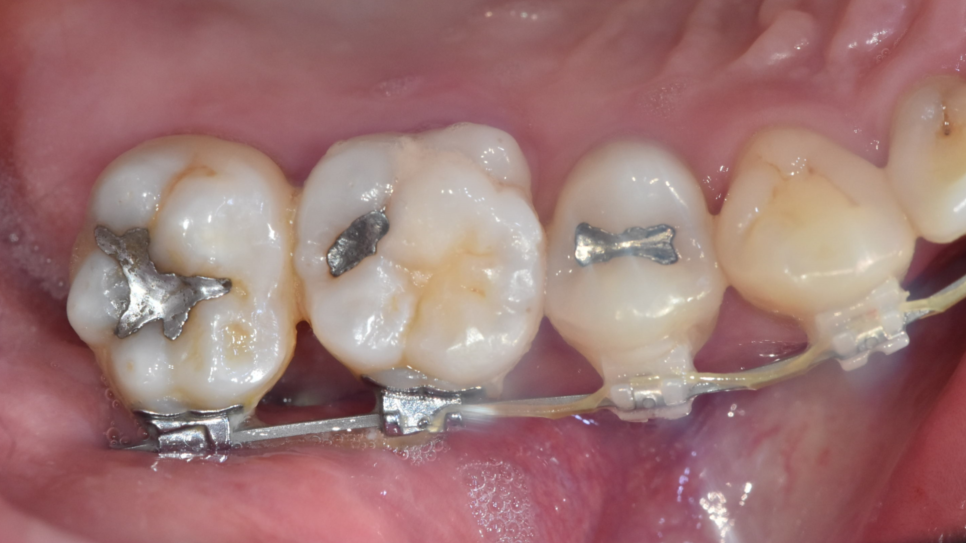

250116 교정 장치가 부착되어있지 않는 씹는면 위치

작은 충치라면

충치의 위치가 장치가 부착되어 있지 않는 씹는 면이라면

교정 중에도 충분히 치료가 가능합니다.